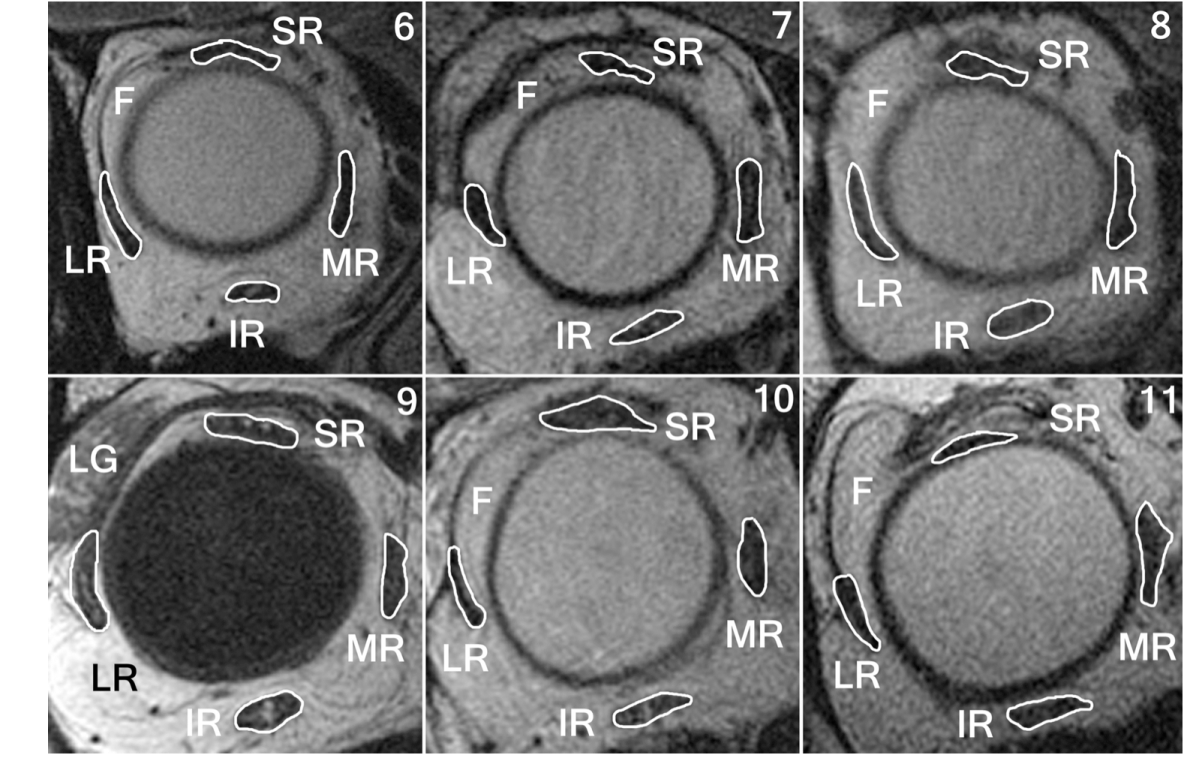

Methods—Eleven strabismic subjects with high myopia underwent ophthalmological examination and orbital magnetic resonance imaging (MRI) to assess quantitative orbital anatomy.

Results—Of 11 subjects, 5 had HES; 6, SES. Mean axial length in subjects with HES was 32 ± 5 mm; in subjects with SES, 32 ± 6 mm. Average distance esotropia in subjects with HES was 61Δ ± 39 ; hypotropia was 26 ± 21 . Average distance esotropia in subjects with SES was 23 ± 57 ; hypertropia was 2 ± 2 . All 5 subjects with HES had superotemporal globe prolapse; the LR-SR band was thinned in 6 orbits and ruptured in 2. The mean angle between the lateral rectus and superior rectus muscles in HES was 121° ± 7°. In SES the LR-SR band was thinned in 7 orbits and ruptured in 5, with superotemporal soft tissue prolapse. The mean angle between the lateral rectus and superior rectus muscles was 104° ± 11°, significantly less than in HES (P < 0.001).

Conclusions—SES occurs in highly myopic patients who also exhibit less relative globe dislocation than in HES. Unlike HES, SES exhibits superotemporal soft tissue prolapse that may limit superotemporal globe shift. The distinction is important because surgery for HES uniquely requires creation of a surgical connection between the superior rectus and lateral rectus muscles, whereas SES may be treated with conventional surgery. SES can cause strabismus in high axial myopia. Orbital MRI is useful in differentiating SES from HES.